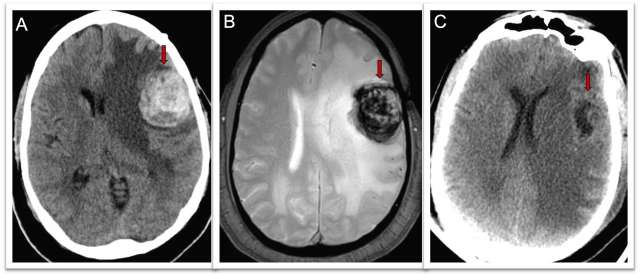

Treatment of a CCM depends on its location and the symptoms it causes (most commonly from bleeding events). Your doctor may recommend monitoring it with MRIs and treating symptoms with medications (Figure 2). If surgical treatment is necessary, the cerebrovascular surgeons at UCLA are expertly trained in this specialized procedure, and have performed a high volume of these surgeries. In each case, we aim to perform these surgeries in the most minimally-invasive way possible, removing the CCM with the least disruption of normal tissue.